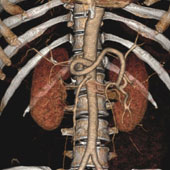

We utilize one of the few 64 slice CT scanners in North Texas that allows non-invasive diagnosis of such conditions as coronary artery disease (heart vessel blockage).  The heart vessels are displayed on our advanced 3D computer workstations where one of our doctors can make a diagnosis in minutes.  This procedure is much safer than cardiac catheterization.

All of our latest generation CT machines have multiple detectors and even greater computer speed. Our CT scanners can image a patient with continuous table movement and multiple simultaneous spiral cuts covering the body in a matter of seconds